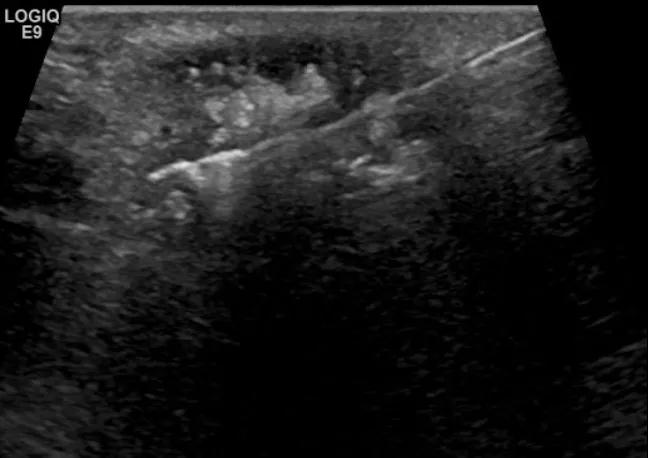

随后,徐栋教授进一步分享了五个临床实战病例,带来了更直观的热消融治疗经验。第一个病例是62岁肺癌患者,术后1年余发现双侧锁骨上淋巴结复发,侵犯神经,存在静脉回流、淋巴回流障碍,肿胀、疼痛非常明显。影像显示患者淋巴结边界不清、形态不规则,存在浸润,血流强化增强。由于患者在系统治疗后进展,且主要目的缓解症状、减瘤。局麻下行热消融术,从后向前逐层消融,热消融之后超声造影即刻评估显示完全充盈缺损,完全覆盖病灶。

(病例1图例)